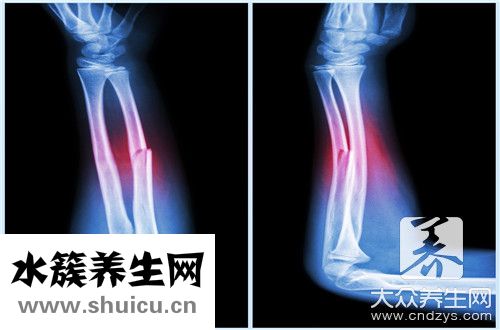

眾所周知,骨折之后,一般要修養三個月。 讓骨骼再次生長需要三個月。 骨折后,必須用石膏固定。 另外,后期最好慢慢開始動作。 如果動作過快,骨頭恢復就會變慢,也有可能對骨頭造成二次傷害。 骨折的話最好躺在床上,用背帶等吊傷口,使血液流通正常,待骨頭長大后再工作。 那么,骨折太早了走路有什么呢?

上肢骨折,進行了有效的固定,下地活動是沒有危害的。下肢骨折后,過早的下地活動,可能會引起骨折的移位或者再次骨折。如果進行了內固定,可以引起內固定物折彎,甚至斷裂。脊柱骨折后,在骨折未愈合之前下地,由于重力的擠壓,可以引起椎體的塌陷,甚至引起壓迫神經,引起麻木等現象。如果已有神經癥狀,可能會使神經癥狀加重。